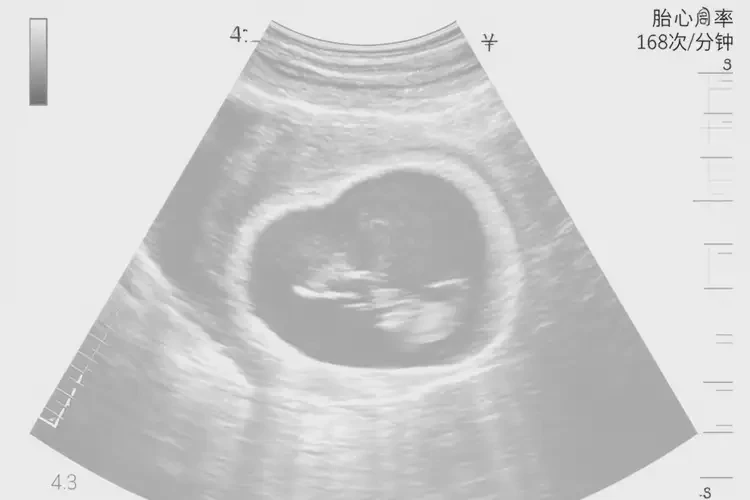

孕3周3天胎心166正常嗎

胎心166次/分鐘在孕3周3天屬于正常范圍

在孕早期,胎兒的心臟開始形成并逐漸發(fā)育,胎心率會(huì)隨著孕周的增加而變化。通常情況下,孕3周3天的胎心率在140-170次/分鐘之間被認(rèn)為是正常的。胎心166次/分鐘在這個(gè)時(shí)間段內(nèi)是正常的。

孕3周3天胎心166正常嗎(圖1)